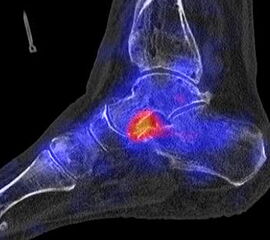

Abbildung 2.1.

Bildbeispiele symptomatische OCL

Zum Lesen der Bildbeschreibung und zur Vollansicht bitte das Bild anklicken. Bild: H. C. Rischke